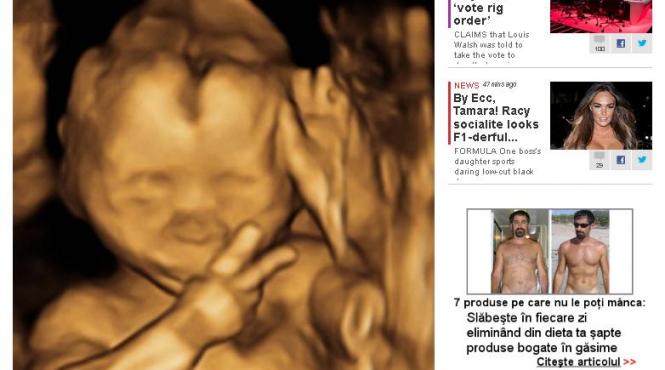

Semnul INCREDIBIL făcut de un bebeluş din pântecele mamei. Cu ce i-a uimit micuţul pe medici